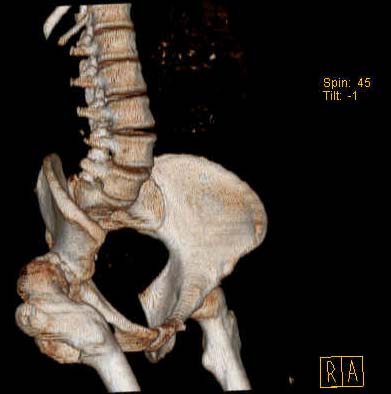

Уважаемые коллеги!Женщина, 35 летВ прошлом по поводу врожденного вывиха бедра перенесла операцию остеотомии по Шанцу

с удлинением правой ноги за счет бедра на уровне диафиза. В последнее время прогрессируют боли в правом тазобедренном суставе, порочное положение правой ноги, затруднена ходьба.Вопросы:1) Целесообразно ли эндопротезирование правого тазобедренного сустава?2) Целесообразный ли следующие действия: канал бедренной кости предполагаем вскрыть для введения ножки протеза на высоте угловой деформации, предполагаем низведение большого вертела с мышцами; протез будет подобран индивидуально, предполагается умеренная версия?В приложении рентгенограммы и трехмерная КТ.В цветном и более качественном варианте КТ размещена здесь